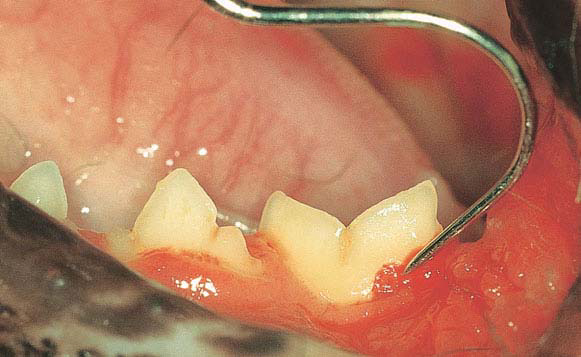

بیماری پریودنتال، یکی از رایجترین بیمارهای دهانی در سگها و گربهها است (تصویر ۱) که بر اثر پلاکهای دندانی ایجاد میشود البته این اصطلاح به تمام بیماریهایی گفته میشود که بافتهای نگهدارنده دندان را درگیر میکنند. التهاب لثه به عنوان اولین علامت شروع بیماری است که در این مرحله امکان بهبودی کامل وجود دارد و قابل برگشت است اما با پیشرفت بیماری بافتهای نگهدارنده دندان آسیب میبیننند. افتادن، لق شدن دندانها، درد، خونریزی، عفونتهای دهانی و مشکل در غذا خوردن از عوارض این بیماری است. و در حالت شدید بیماری پریودنتال سبب گسترش عفونت و باکتری به خون شده و میتواند با آسیب به قلب و کلیه باعث ایجاد اندوکاردیت و گلومرولونفریت گردد.

بله، همانطور که گفته شد در بیماری پریودنتال گاهی عمق Sulcus دندانی افزایش مییابد و دندان لق میگردد که امکان افتادن آن نیز وجود دارد. در گربه بیماری تحت عنوانFORL (Feline Odontoclastic Reoptive Lesions) وجود دارد و عمدتا گربههای بالای ۵ سال را درگیر میکند (تصویر ۲). در این بیماری دندان گربه از قسمت گردن یا پایه با فعال شدن سلولهایOdontoclastic خورده میشود در این حالت در معاینه بالینی با دندانی مواجه میشویم که لثه بالاتر ازدندان و یا روی دندان قرار گرفته است. عمدتا رادیوگرافی در تشخیص این بیماری کمک کننده است. این گربهها عمدتا در خوردن غذا مشکل داشته، ریزش بزاق (خون آلود) و درد فراوانی دارند.